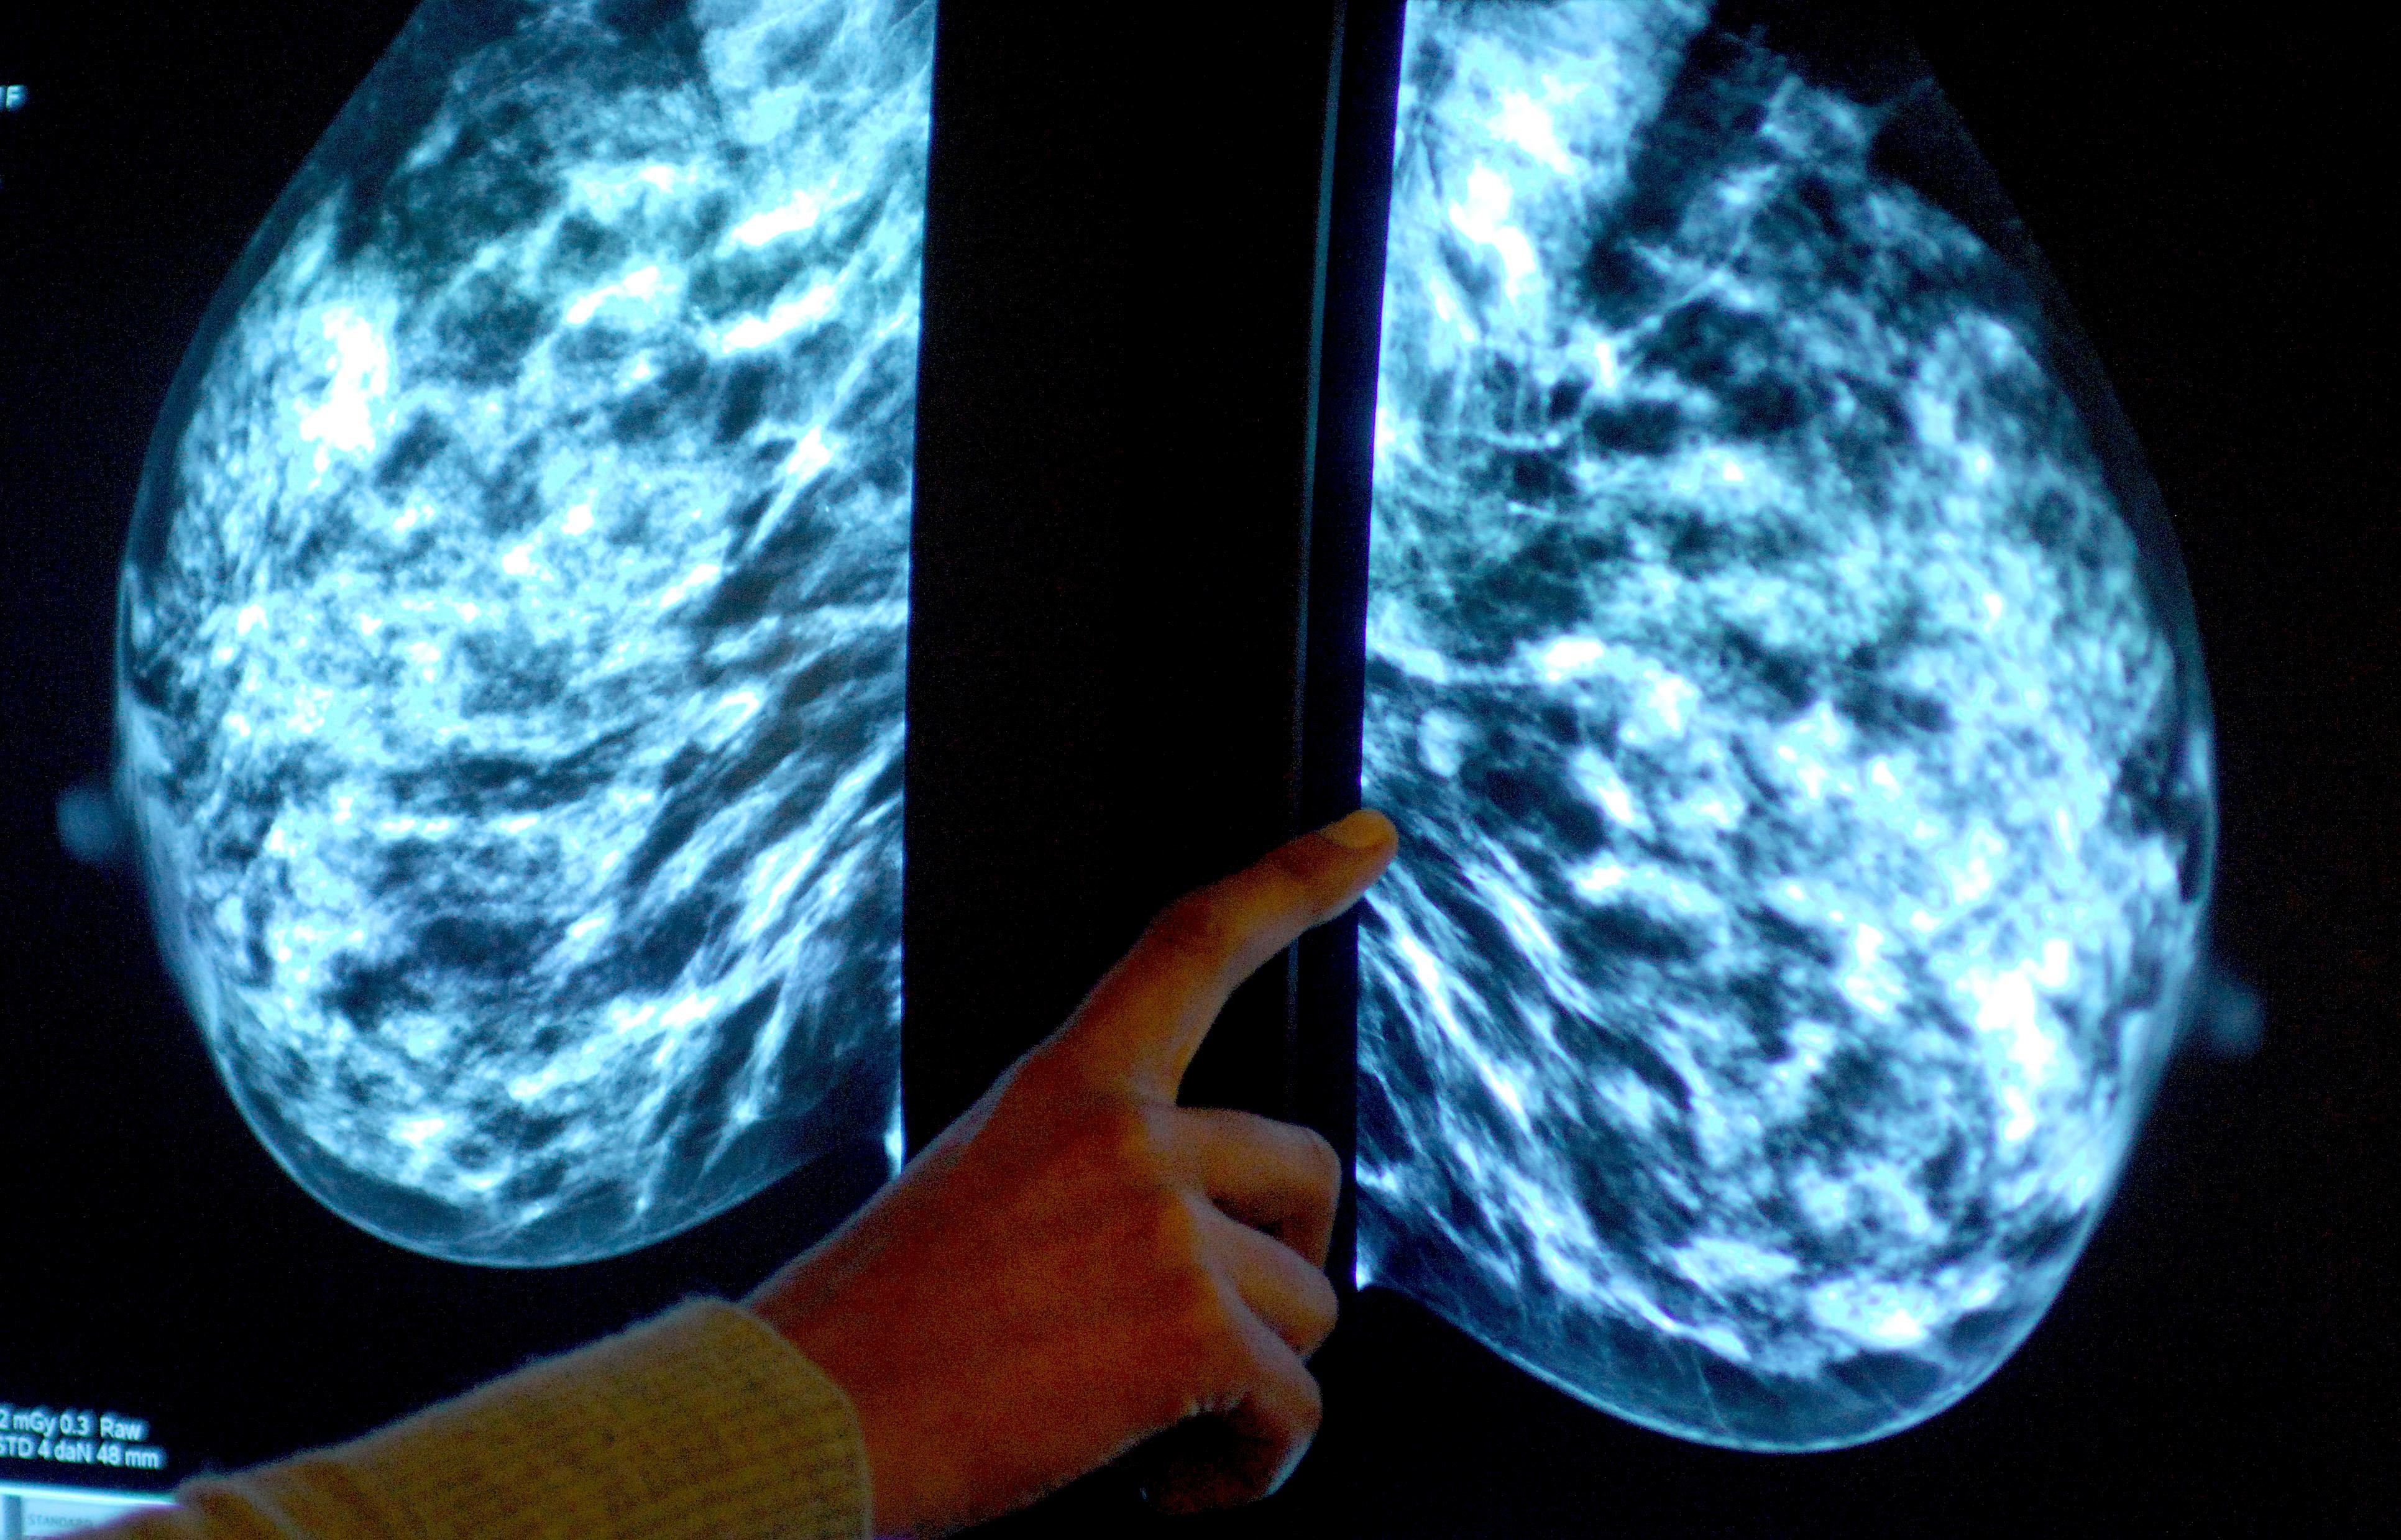

More women in Gloucestershire undergo breast cancer screening – as NHS England target met for first in five years

Breast screening uptake in Gloucestershire remains below pre-pandemic levels